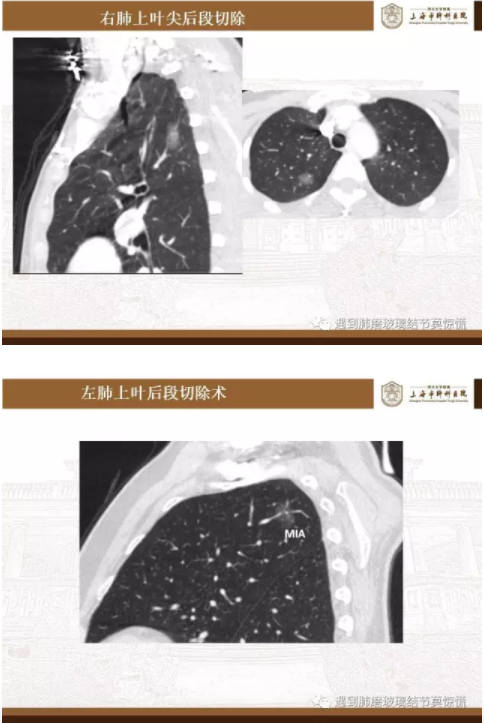

下面就我们的病例分析一下怎么进行肺段切除。

MIA= 微浸润腺癌   IA= 浸润性腺癌   AIS= 原位腺癌   AAH= 不典型腺瘤样增生